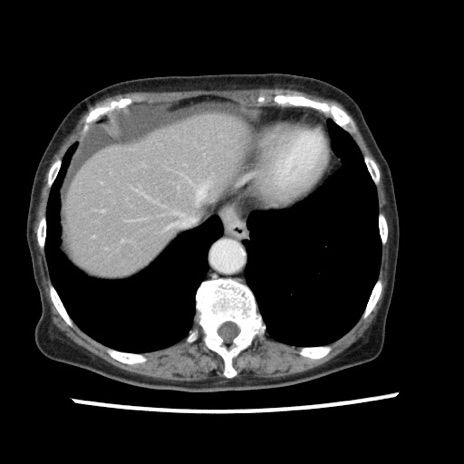

冠状断像

【症例】80歳代女性

【主訴】腹痛

【現病歴】8時間前から腹痛あり来院。

【既往歴】糖尿病、脂質異常症、子宮体癌にて子宮全摘術

【身体所見】意識清明・会話良好だが腹痛で苦悶様、全腹部にわたって反跳痛と圧痛あり

【データ】WBC 13600、CRP 0.14、LDH 224、CK 90